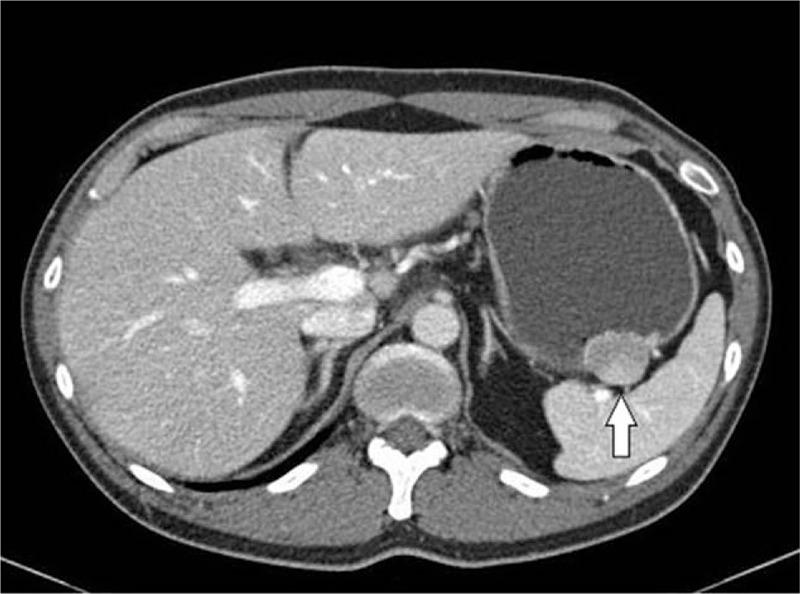

A 45-year-old man, who was incidentally discovered asymptomatic subepithelial tumor (SET), by endoscopy, on the greater curvature of the upper gastric body, was referred to our hospital for further evaluation.

一名45岁男性,在内镜检查时偶然发现胃体上部大弯处有无症状的上皮下肿瘤(SET),遂转诊至我院进一步评估。